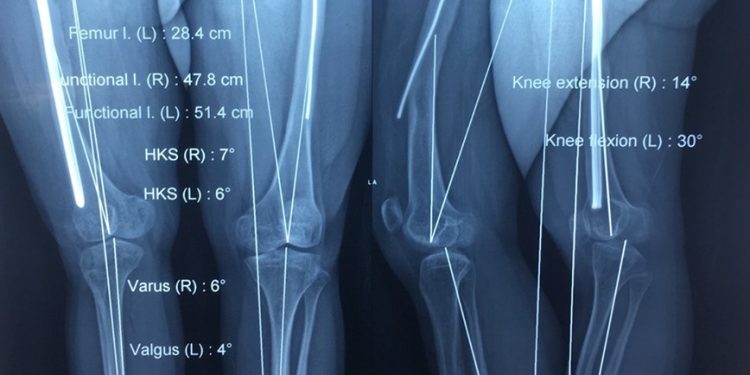

Ngày 02/6/2019, BS Phan Văn Tiếp – Chuyên gia phẫu thuật chỉnh hình nhi TP. Hồ Chí Minh và BSCKII Phạm Đình Thành – Phó khoa Ngoại Chấn thương chỉnh hình & bỏng Bệnh viện Đa khoa tỉnh Khánh Hòa và ê kip phẫu thuật đã mổ chỉnh trục & kết hợp xương đùi trái bằng đinh nội tủy Kuntcher; đồng thời cắt đinh trồi của xương đùi phải cho bệnh nhân Trịnh Nguyễn Bảo Th., sống tại Phường 12, Quận Gò Vấp, TP.Hồ Chí Minh.

Bệnh nhân có tiền sử xương bất toàn hay thường gọi là “xương thủy tinh”.Mặc dù 21 tuổi nhưng bệnh nhân chỉ cao 130cm. Bố mẹ phát hiện bệnh ngay khi sinh con mình ra đời, lúc đó bệnh nhi bị gãy xương. Trong suốt chặng đường phát triển củaTh. đã trải qua mấy chục lần phẫu thuật đến nỗi mẹ bệnh nhân không còn nhớ chính xác số lần đưa con mình vào phòng mổ.

Lần này mẹ Th. phải theo BS Tiếp ra Bệnh viện đa khoa tỉnh Khánh Hòa vì trong TP.Hồ Chí Minh không có đinh nội tủy khớp với kích thước ống tủy xương đùi của bệnh nhân! Sau mổ bệnh nhân đang được hồi sức, theo dõi chăm sóc đặc biệt vì bệnh nhân được thực hiện 2 đại phẫu trong một lần mổ! Lại một loại bệnh lý bẩm sinh do di truyền!